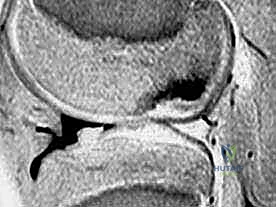

Magnetic Resonance Imaging (MRI)

MRI is our gold standard for cartilage evaluation, boasting high sensitivity and specificity.

* Sequences: Clinically proven cartilage-sensitive sequences include T1-weighted gradient echo with fat suppression and fast spin-echo sequences with and without fat suppression. These protocols allow us to detect full- and partial-thickness lesions, as well as osteochondritis dissecans, even when clinically silent.

* Utility: MRI helps us characterize the lesion size, depth, and the integrity of the subchondral bone, which is vital for surgical planning. It can also detect associated pathologies like meniscal tears or ligament injuries.